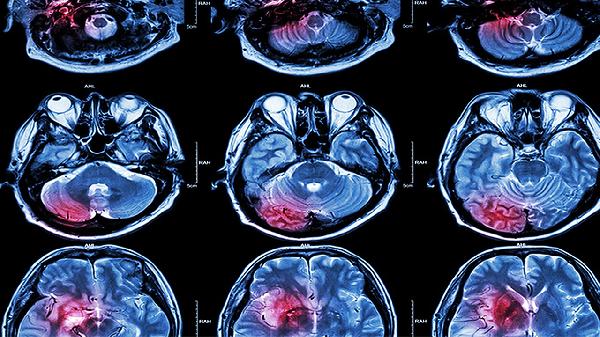

三七粉的主要活性成分三七皂苷能抑制血小板聚集,降低血液黏稠度,促进脑部血肿吸收。对于恢复期脑溢血患者,在医生监测下使用可能帮助改善脑组织供血,减轻神经功能缺损。临床常用血塞通注射液(含三七总皂苷)辅助治疗出血性中风后遗症,但口服三七粉的疗效证据尚不充分。